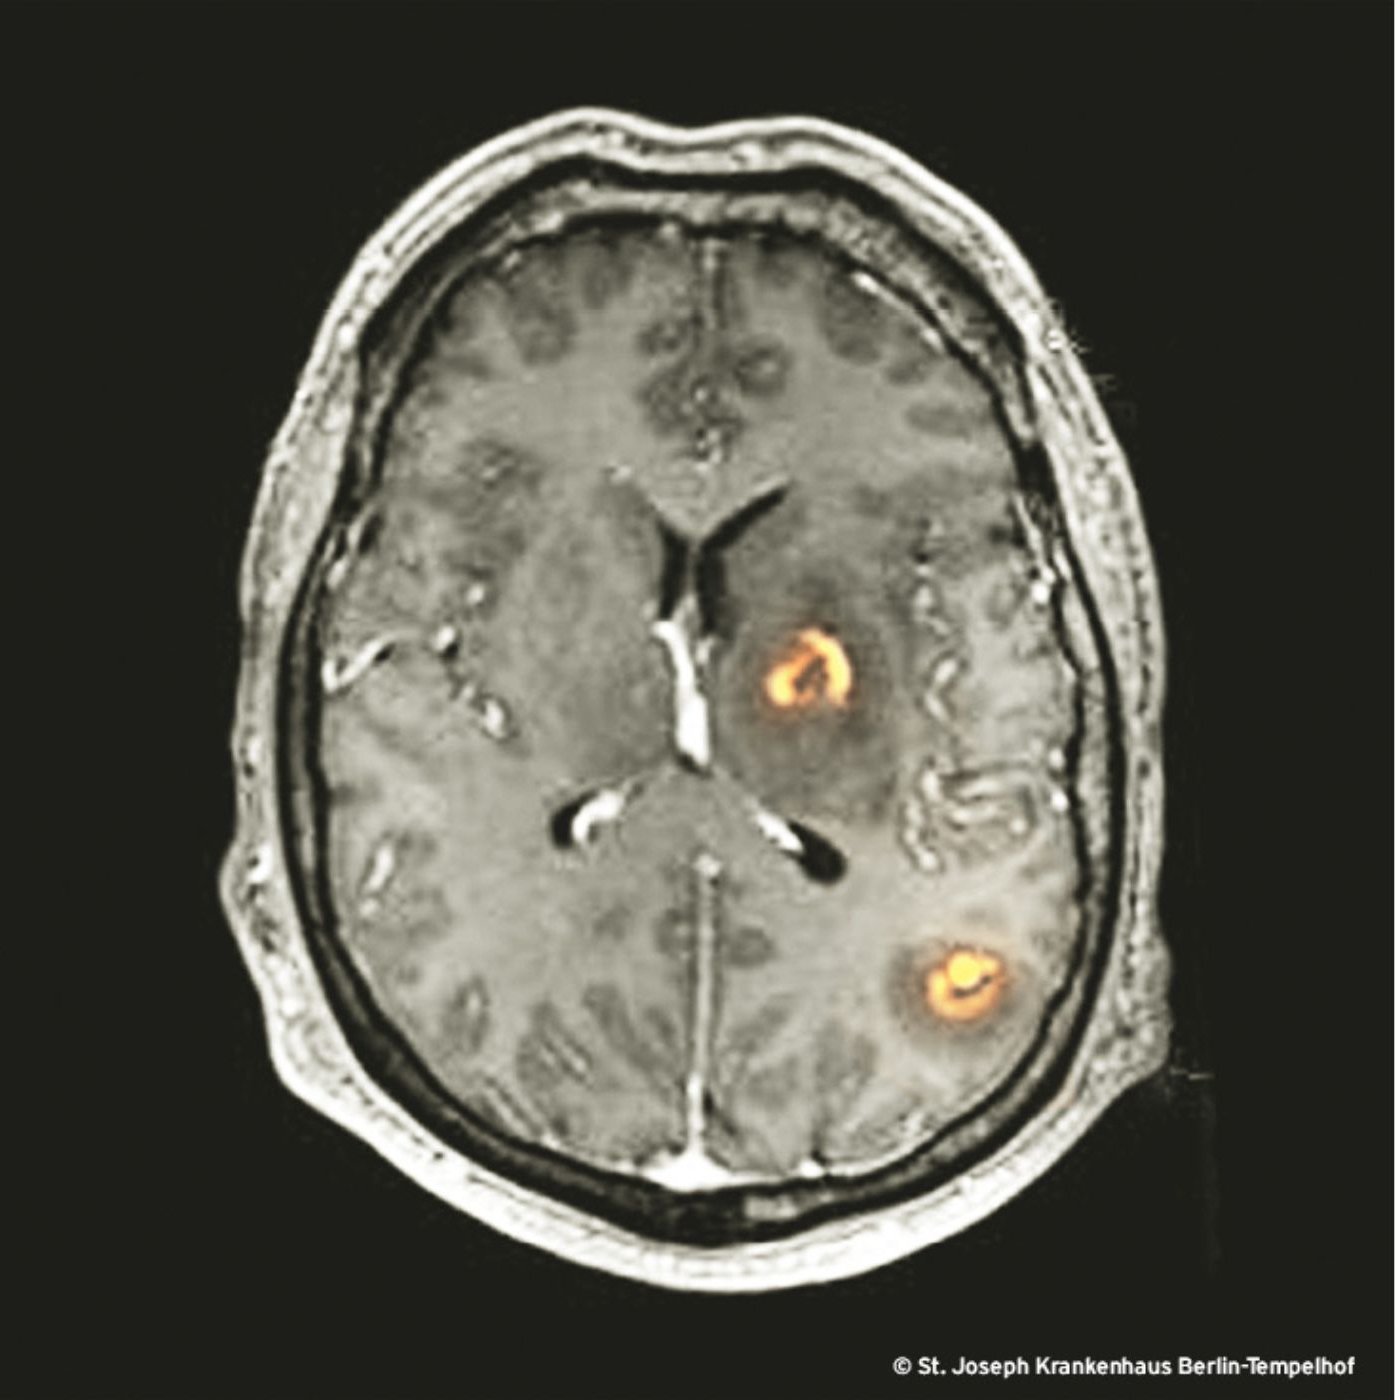

Patient*innen mit undiagnostizierter HIV-Infektion gelangen zur Abklärung solcher Läsionen immer wieder in Kliniken für Neurochirurgie, wo sie mit der Verdachtsdiagnose »metastasierte Tumorerkrankung« operiert oder biopsiert werden. Wie im Falle unseres Patienten (oraler Soor, Panzytopenie), finden sich oft - neben den zerebralen Herden - weitere HIV-Indikatoren, die eine Chance bieten, die HIV-Infektion zu diagnostizieren und den neurochirurgischen Eingriff abzuwenden.

Dritte Ausnahme: Wenn das Immunsystem eines bereits infizierten Menschen im Rahmen einer HIV-Infektion oder einer Chemotherapie geschwächt wird, kann sich die Toxoplasmose zu einer zerstörerischen Enzephalitis - wie bei unserem Patienten - auswachsen [7].

Unser Fallbericht will als Appell gelesen werden, bei allen Patient:innen mit multiplen, ringförmig-kontrastmittelanreichernden Herden mit raumforderndem Umgebungsödem VOR dem Einsatz des Messers nach HIV-Indikatoren zu suchen und einen HIV-Test durchzuführen. Die medikamentöse Therapie der TE ist erfolgreich und zuverlässig wirksam und bewahrt den Menschen vor den Folgen des neurochirurgischen Eingriffs!